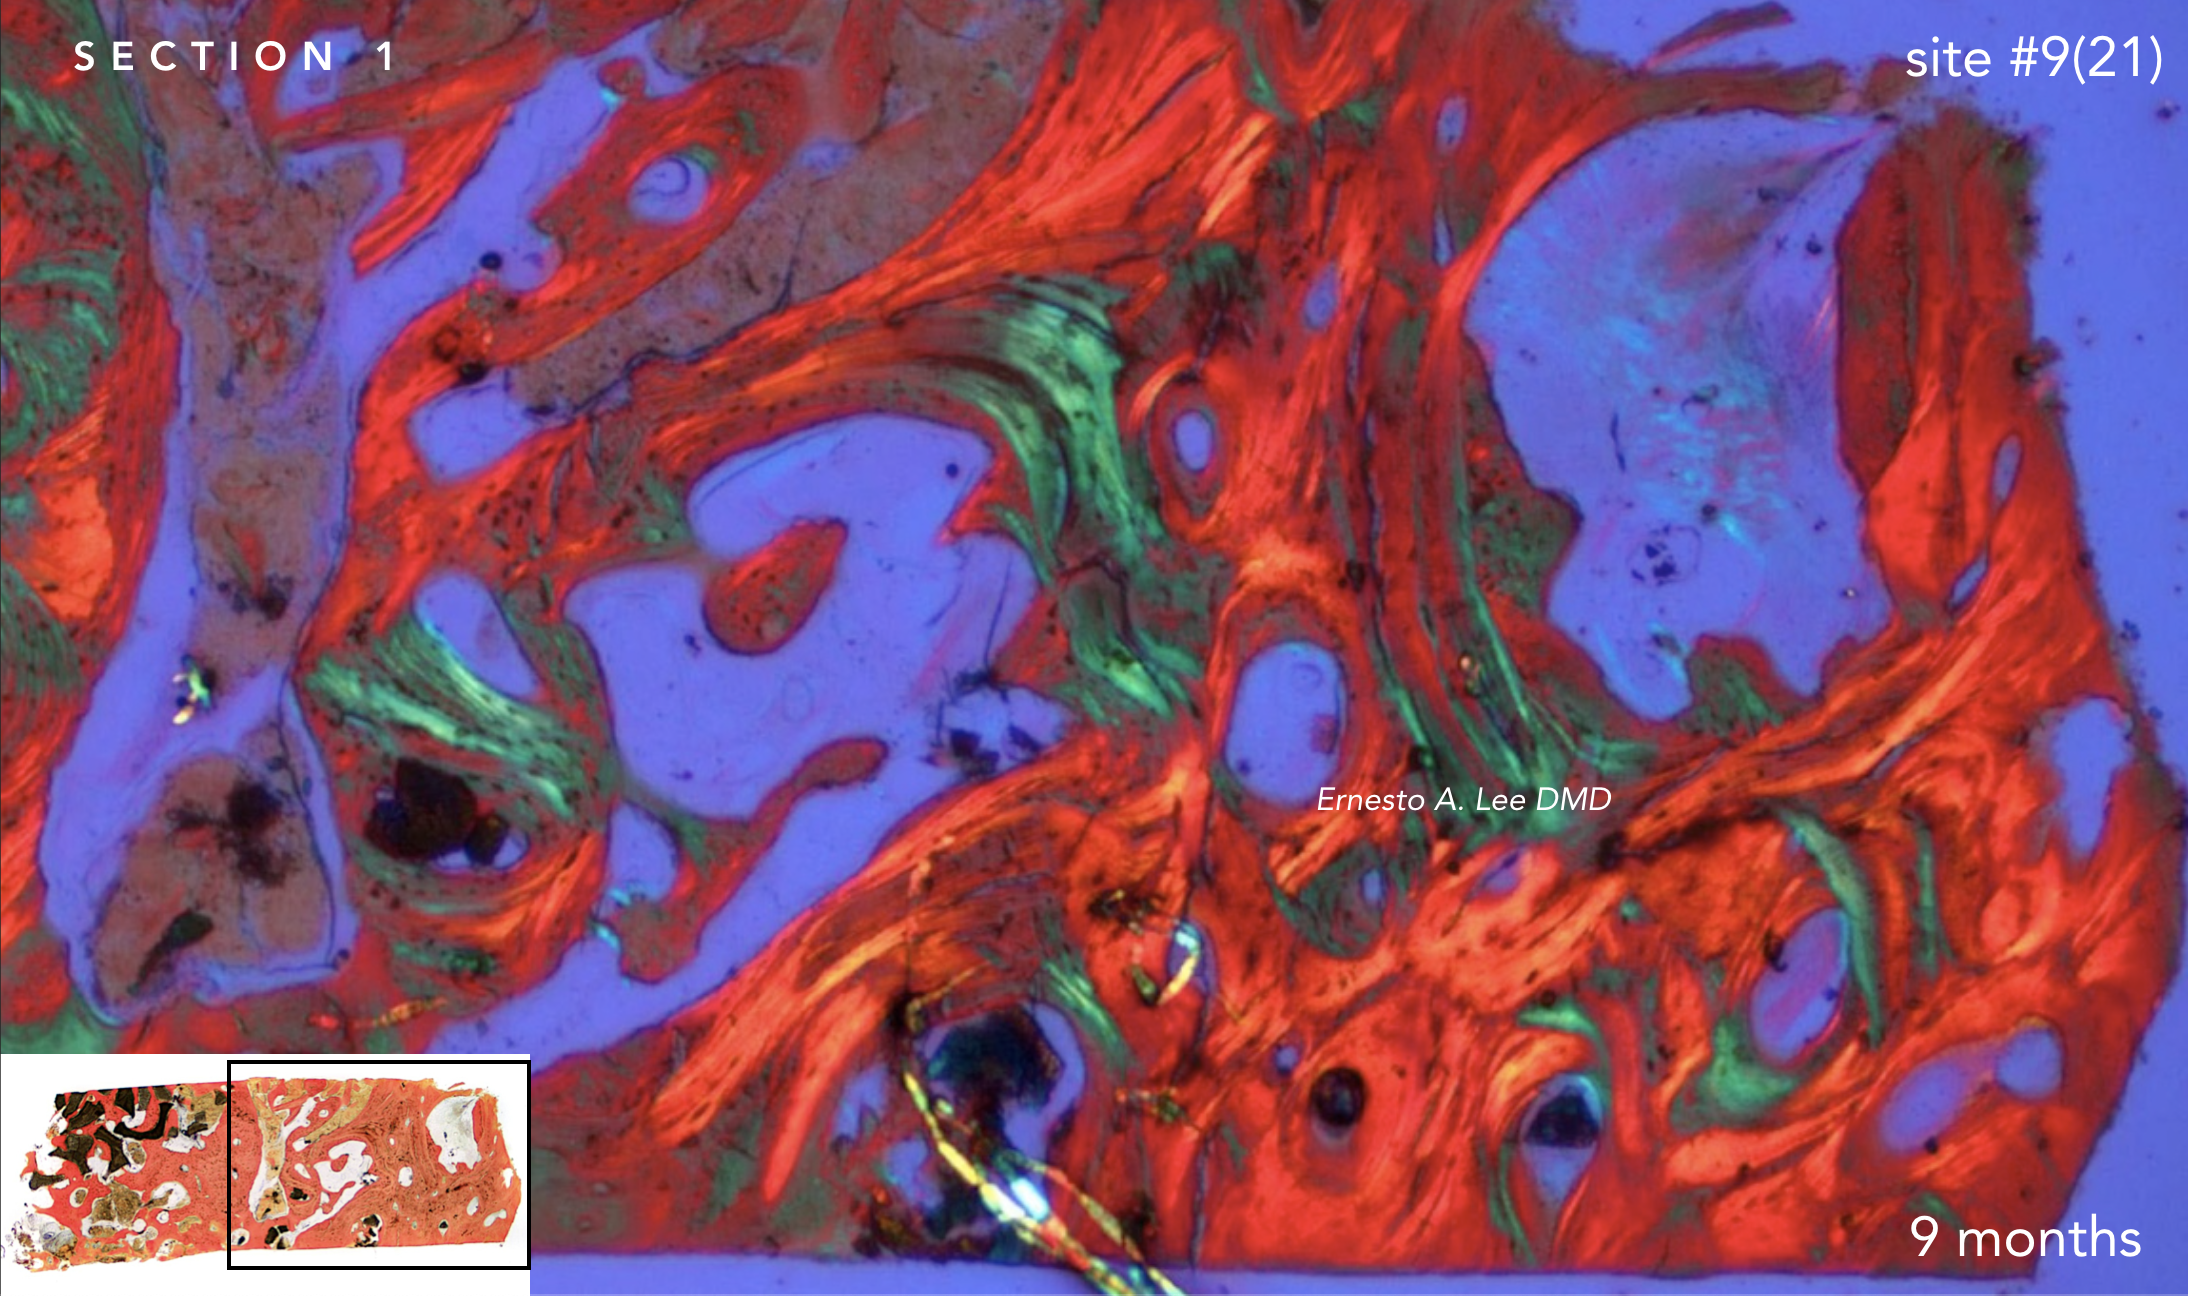

With the patient’s consent, a core specimen was harvested during the osteotomy preparation for implant #9(21) and sent for histologic analysis.

The interstitial and concentric lamellar bone patterns observed are consistent with the appearance of healthy, orderly, living bone.

With the patient's authorization, a specimen was harvested during the osteotomy preparation for implant on site #9(21) and sent for histologic analysis.